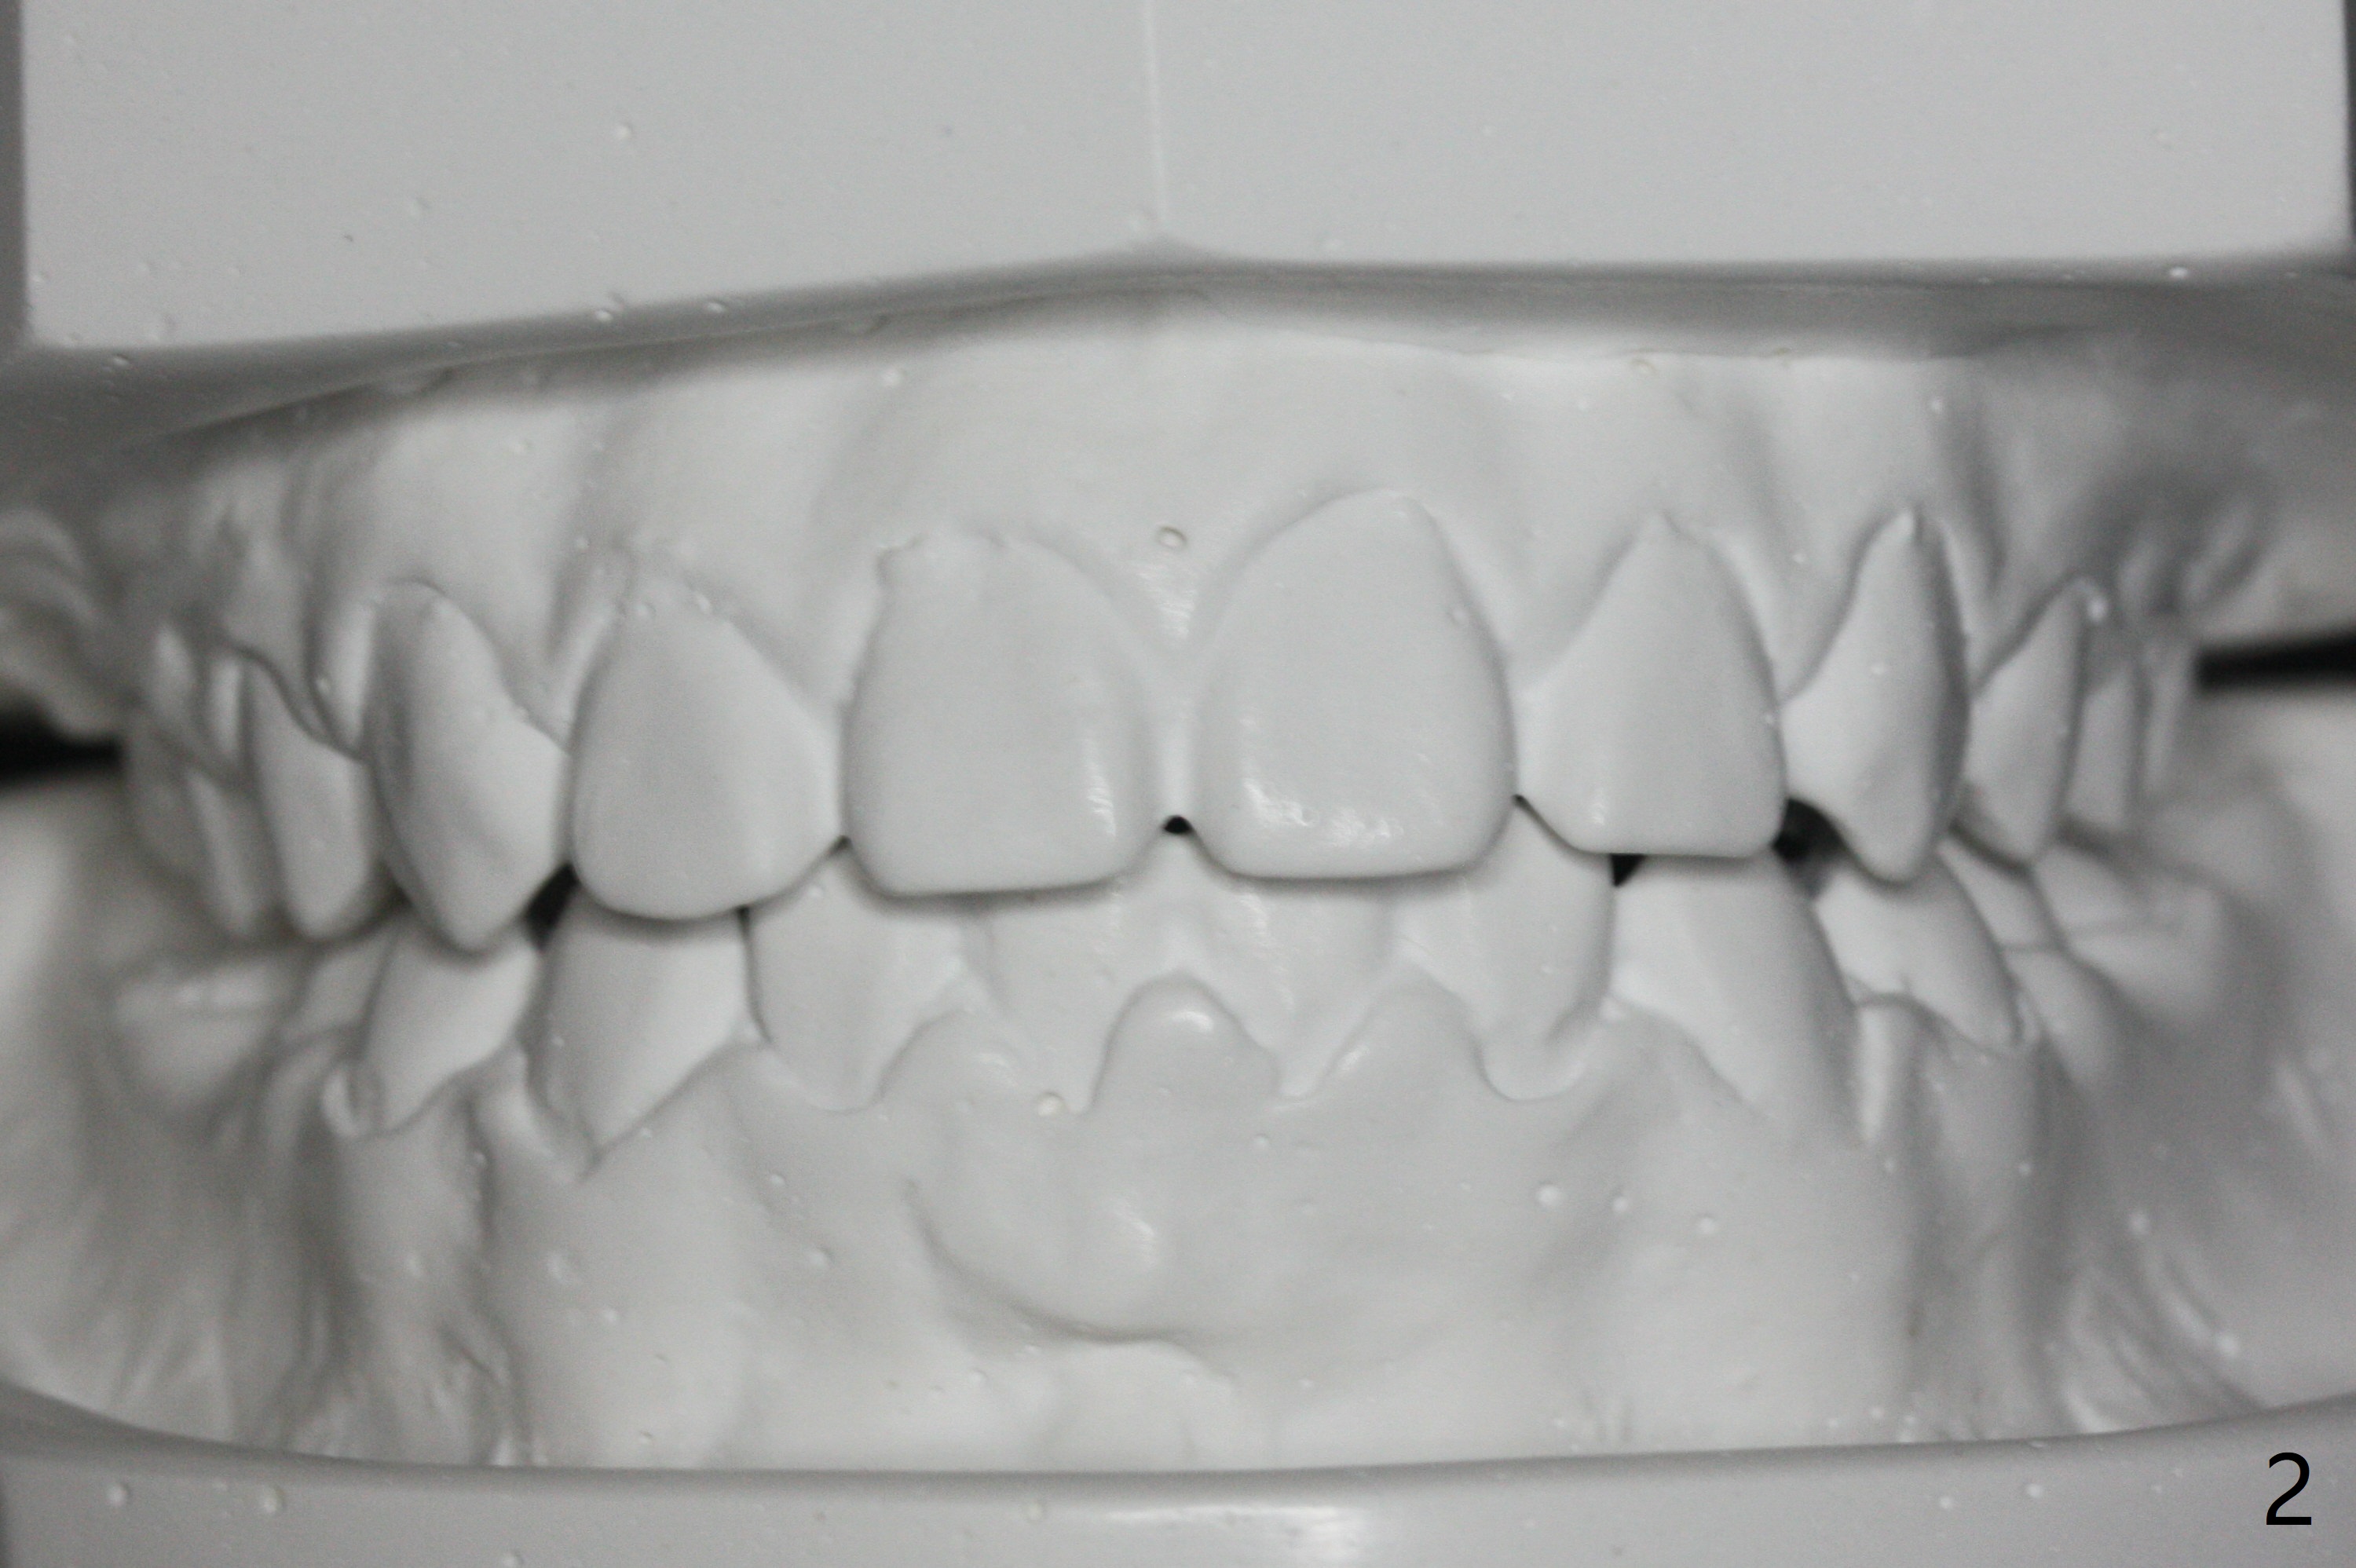

A 11-year-old man starts orthodontic treatment and finishes in 9 months. Two years later crowding relapses because of loss of suck down retainers. It appears that lingual retainer is necessary.